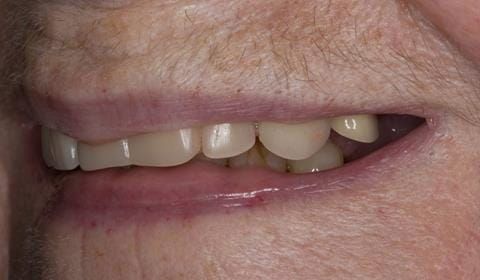

Following consultation and second discussion appointment the patient chose to have option 2 namely, a window denture - maxillary cobalt chromium based partial denture. The clinical situation and treatment process is shown in detail below with photographs. The patient was successfully rehabilitated with this and her quality of life considerably improved. The clinical work was provided by Finlay and the technical work by Rowan.